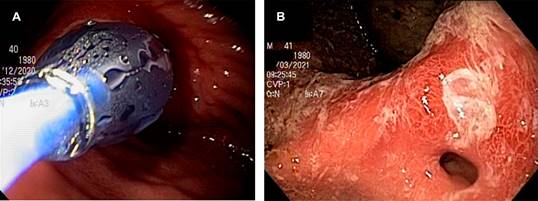

La última endoscopia de control mostró disminución del tamaño de la úlcera ya en fase de cicatrización, con adecuado paso del endoscopio a través del píloro; se realizaron múltiples biopsias de la zona de la cicatriz de la úlcera sin observarse proceso neoplásico maligno activo (Figura 2).

Figura 2: Imágenes endoscópicas de porción antral gástrica. A) Úlcera prepilórica Forrest III con bordes elevados eritematosos de aspecto inflamatorio, en menor medida que el estudio anterior, y estenosis puntiforme pilórica, por lo que se realizó dilatación hidroneumática. B) Disminución del tamaño de la úlcera ya en fase de cicatrización, adecuado paso del endoscopio a través del píloro a los tres meses.